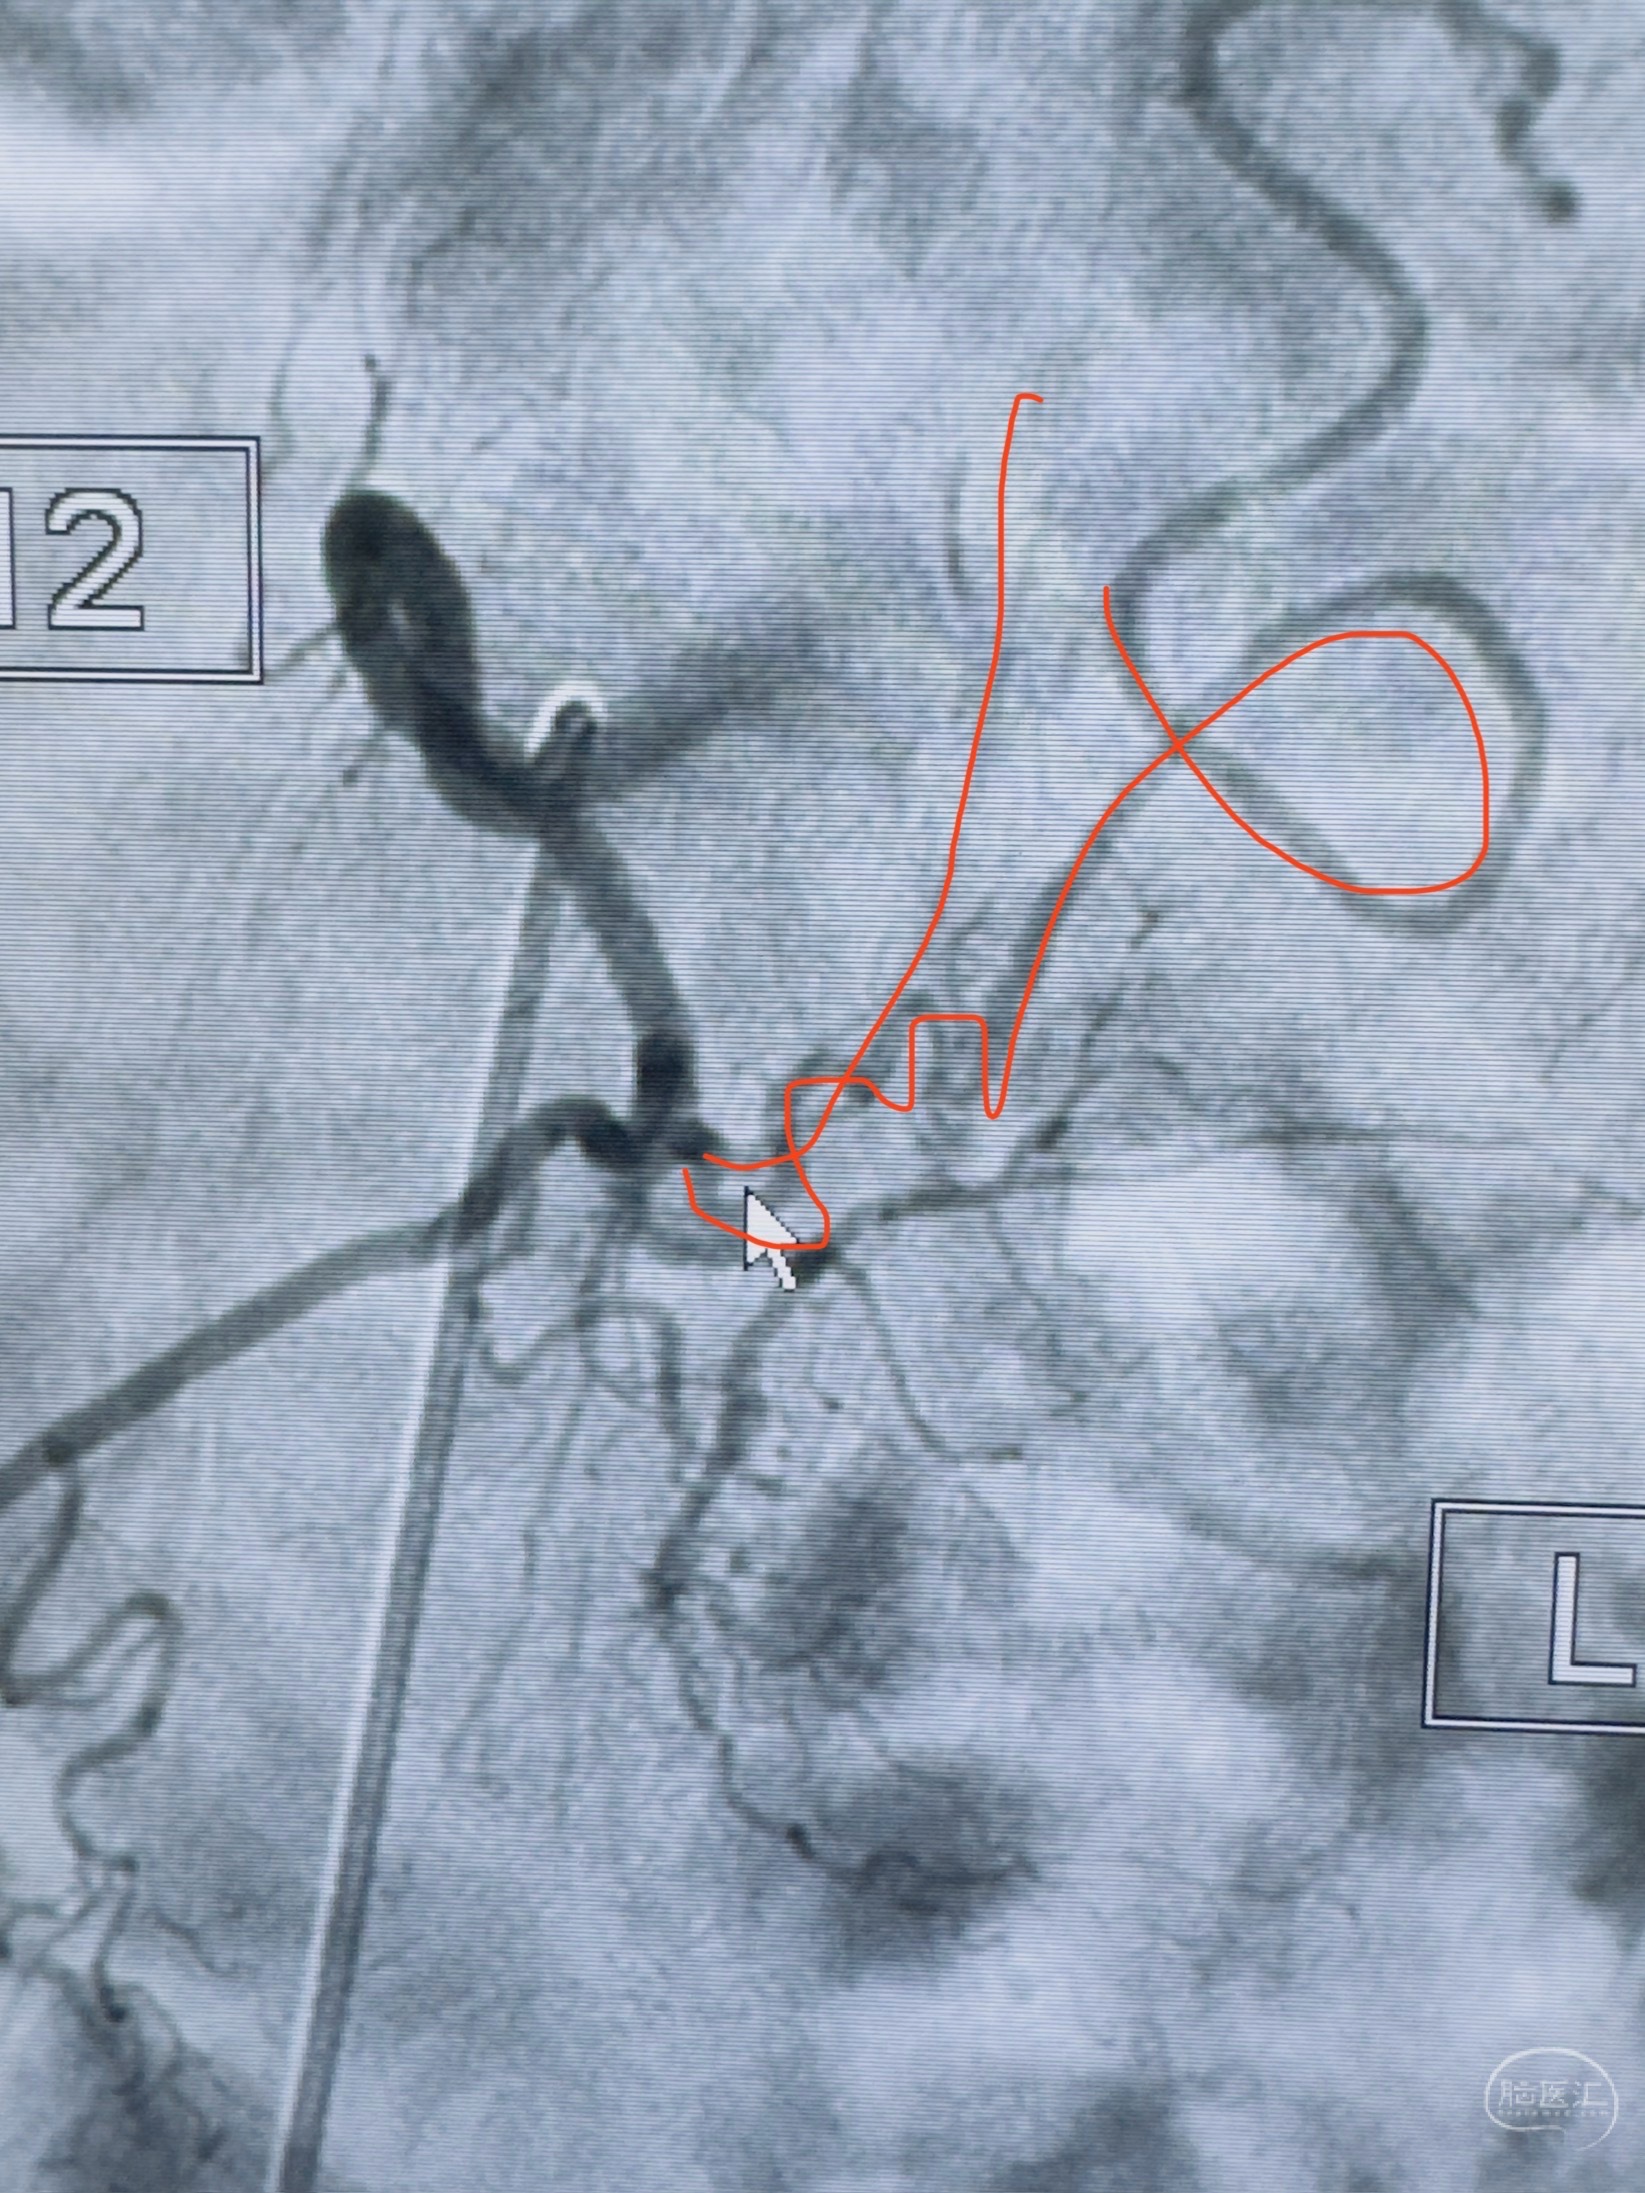

2023-10-13DSA:右侧L1水平硬脊膜动静脉瘘,供血动脉为右侧L1,附近动脉未见明确吻合供血,供血动脉处可见脊髓前动脉发出